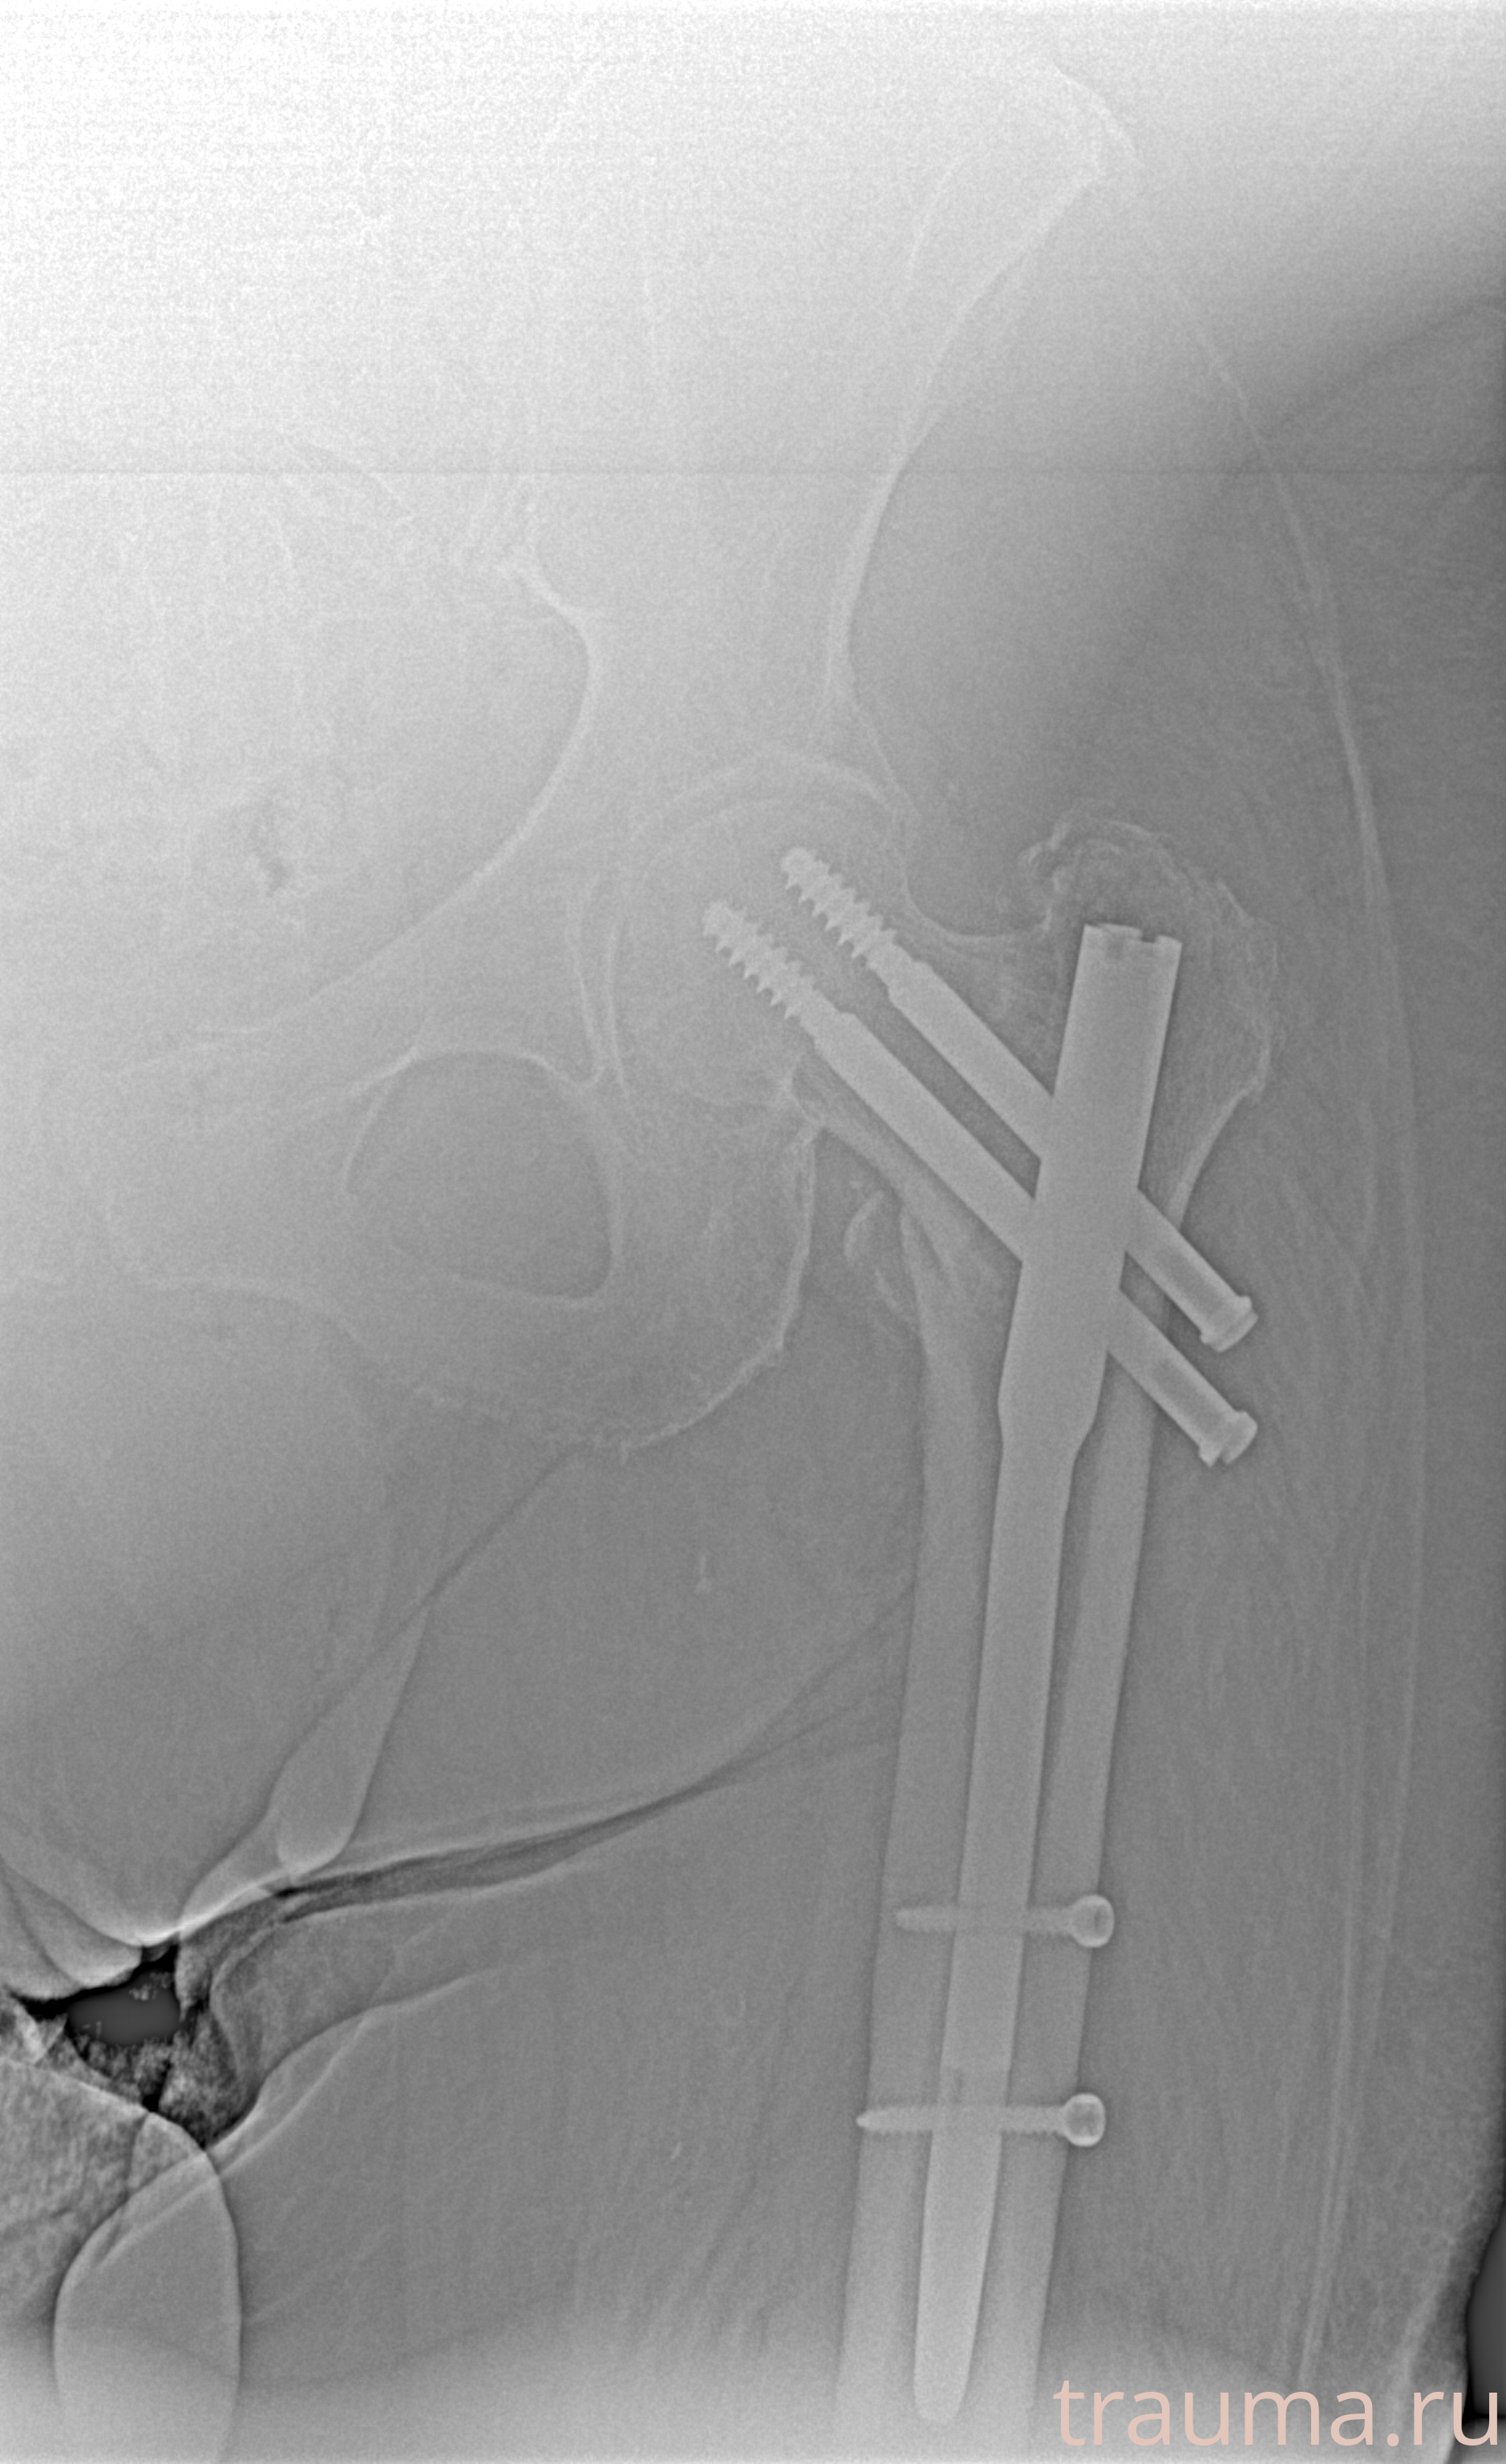

Рентгенограммы

Рентген на дому: по вашему адресу приезжает врач-рентгенолог, травматолог-ортопед с мобильным рентгеновским аппаратом, проводит диагностику травмы или заболевания, делает необходимые рентгенограммы, дает рекомендации по дальнейшему лечению. Получить качественные снимки в домашних условиях возможно благодаря уникальной методике, разработанной МосРентген Центром для института  Склифосовского